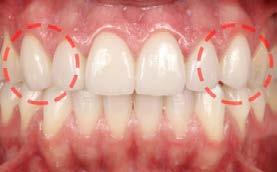

Entre los elementos que conforman al sistema estomatognático, están los dientes caninos, órganos dentales esenciales en la fisiología masticatoria; punto de unión y continuidad estética entre la línea de la sonrisa y el corredor posterior del arco dental, además de que ejercen la función de pilares estabilizadores en la oclusión fisiológica (Figura 1).

Los caninos son indispensables durante los movimientos de lateralidad y vitales para la continuidad de los arcos dentales, tanto en la dentición decidua como en la permanente; son responsables del funcionamiento y la armonía oclusal. Su posición adecuada en el arco asegura un buen contorno de la cara, sonrisa agradable y armónica con la estética facial. (Figura 2).